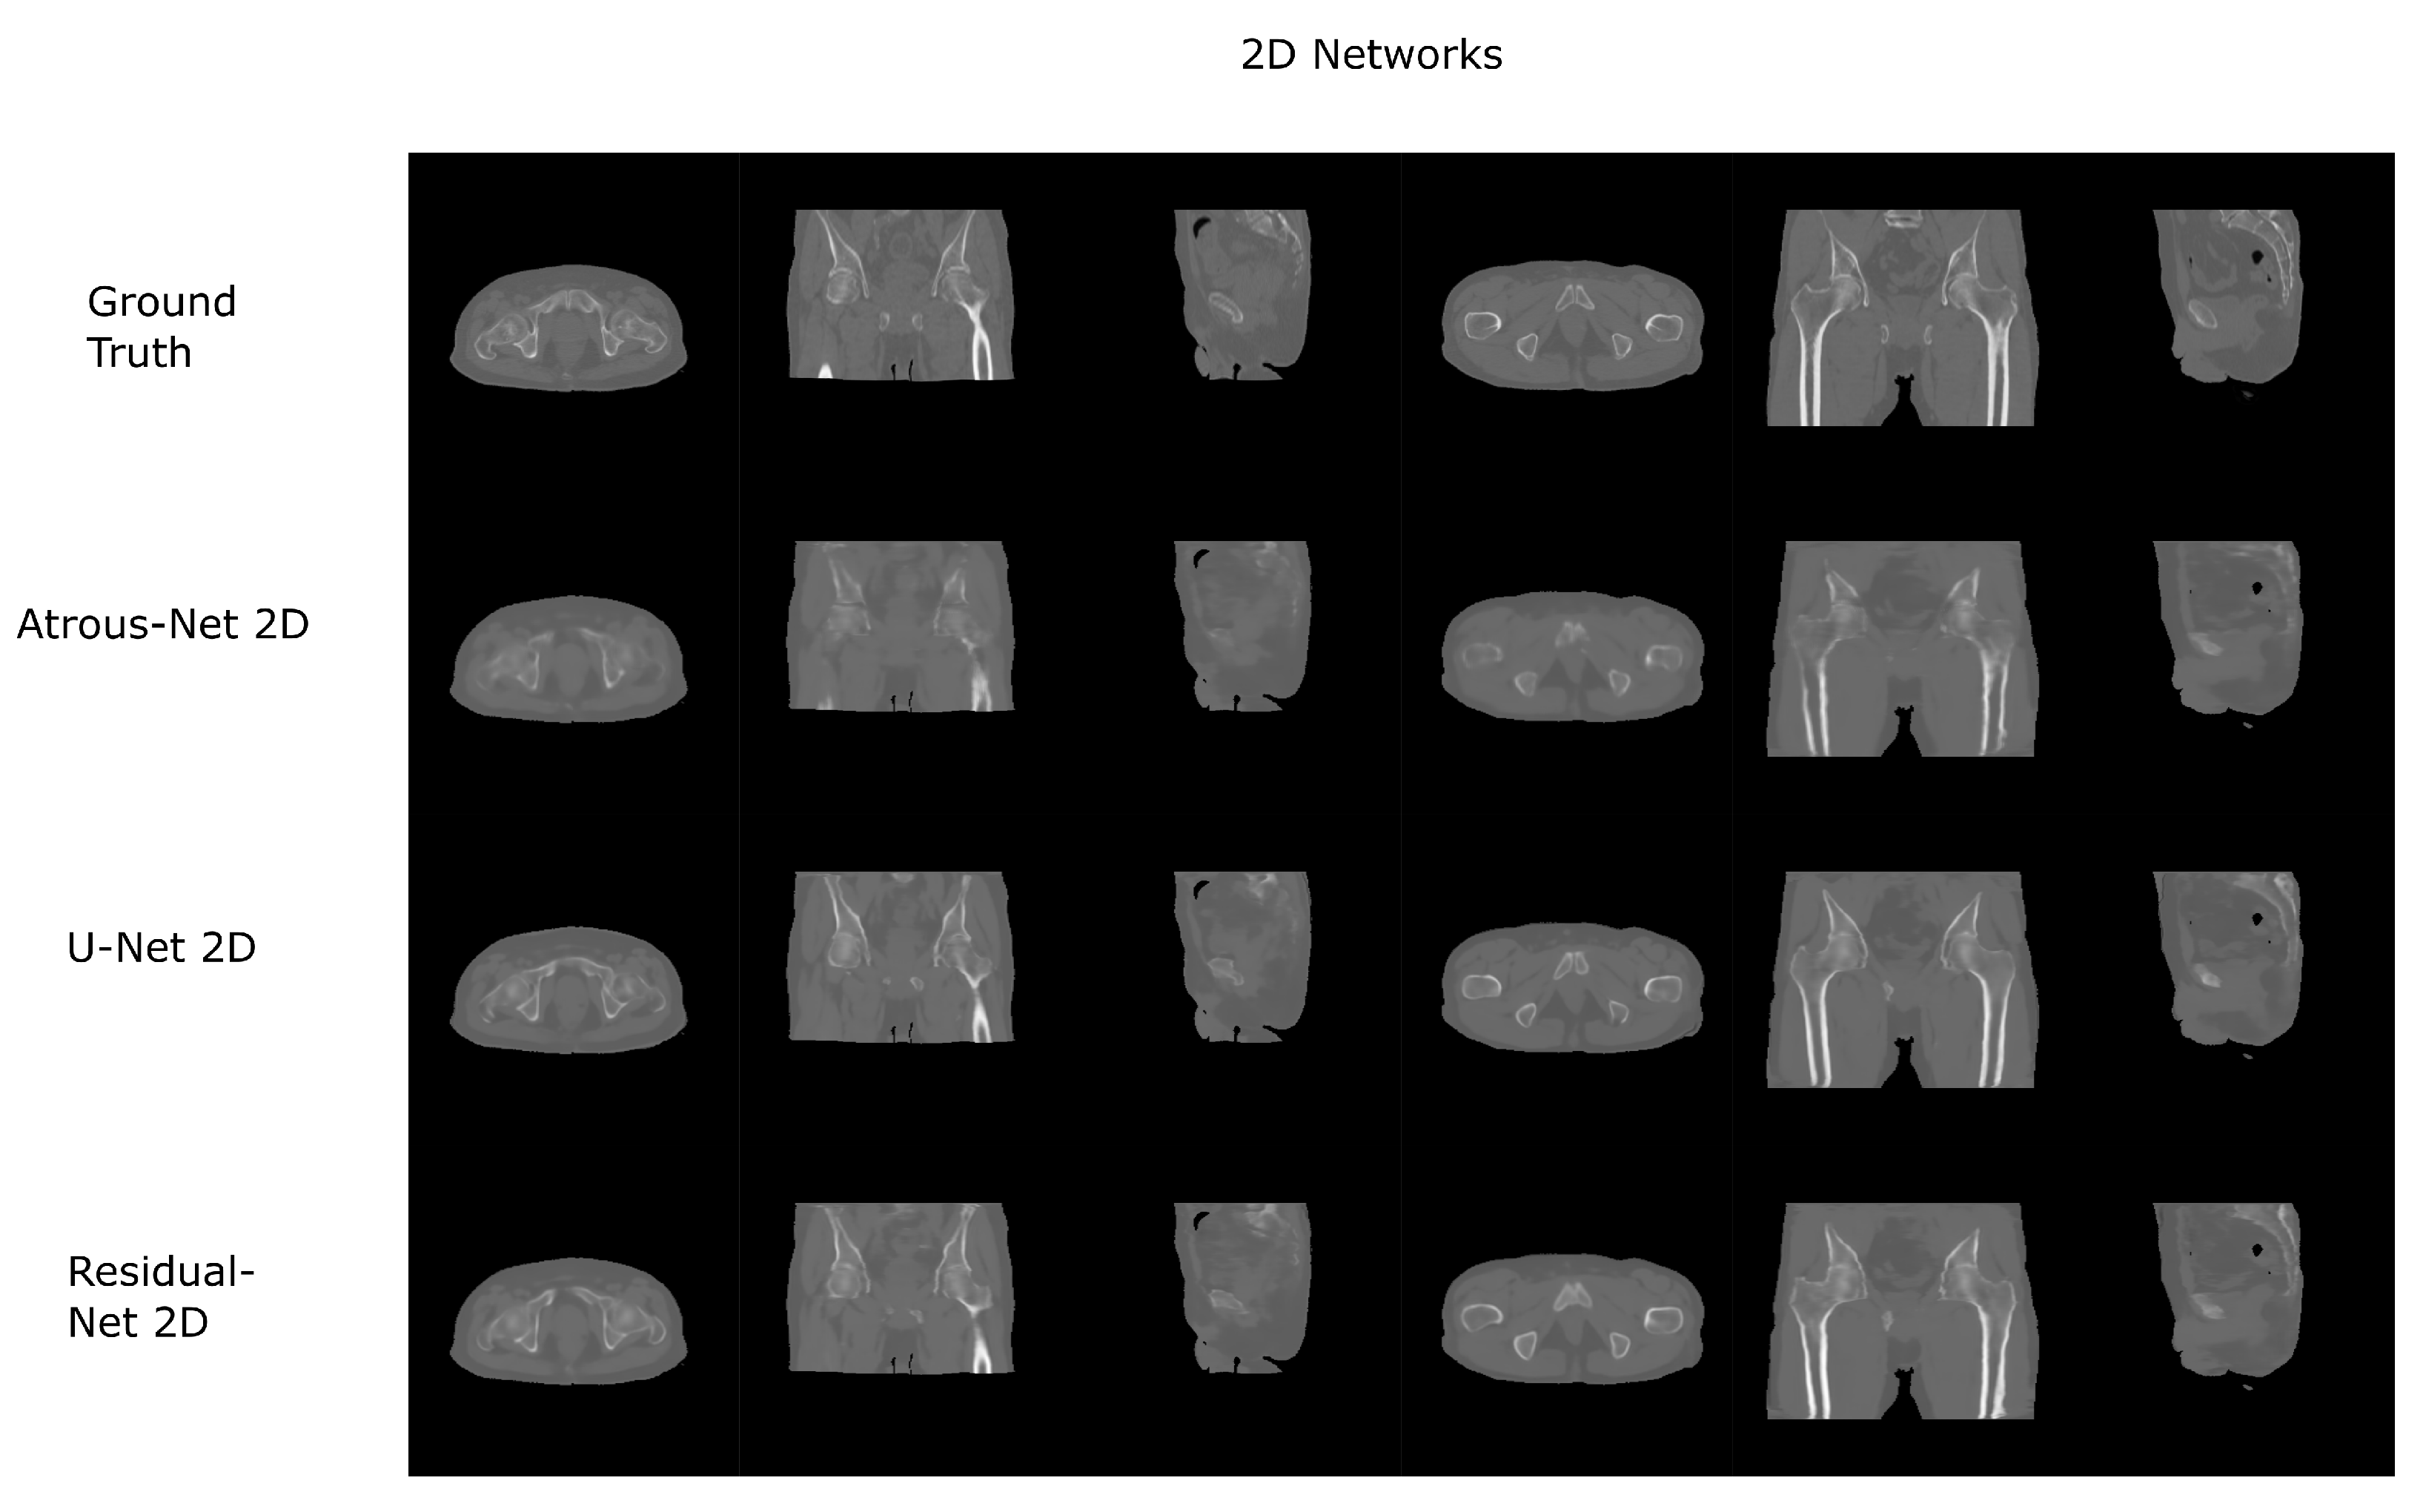

3.1. Head Dataset Results

The results for all tissues using the head dataset are depicted in Table 1, Table 2 and Table 3; the results using only the bone voxels are detailed in Table 4, Table 5 and Table 6; the results using only the fat voxels are detailed in Table 7, Table 8 and Table 9; and the results using only the soft-tissue voxels are detailed in Table 10, Table 11 and Table 12. The best performing 2D network for the head dataset was the Residual-net. The results presented a MAE of 99.83 HU, a PSNR of 24.83 and a Pearson Coefficient of 0.931 in all tissues, and a MAE of 326.33 HU, a PSNR of 19.04 and a Pearson Coefficient of 0.826 in bone voxels. The ANOVA test revealed a statistically significant effect of the 2D architectures for MAE results (all tissues: F 2 , 36 = 91.1 , p < 0.001 ; bone: F 2 , 36 = 74.2 , p < 0.001 ) and PSNR results (all tissues: F 2 , 36 = 99.3, p < 0.001 ; bone: F 2 , 36 = 85.6, p < 0.001 ). A paired t-test was used to compare the Residual-net to the other networks reporting also statistically significant differences in the MAE and in the PSNR (Table 13). Using 2D convolutions, the Atrous-net and the U-net performed 5% and 18% worse than the residual-net, respectively. Moreover, the U-net network was clearly behind the other networks using 2D convolutions. Nevertheless, the U-net in 3D-16 obtained a MAE of 89.54 HU, a PSNR of 25.69 and a Pearson Coefficient of 0.943 in all tissues, and a MAE of 289.10 HU, a PSNR of 20.05 and a Pearson Coefficient of 0.861 in bone voxels, which were the best results for the head dataset. The ANOVA test also reported a statistically significant effect of the 3D networks for the MAE (all tissues: F 2 , 36 = 63.2 , p < 0.001 ; bone F 2 , 36 = 189.8 , p < 0.001 ) and the PSNR (all tissues: F 2 , 36 = 10.5 , p < 0.001 ; bone: F 2 , 36 = 83.1 , p < 0.001 ). The post hoc paired t-test that is depicted in Table 14 also reported statistically significant differences in the MAE and PSNR after comparing each architecture. Summarizing, the results using 3D convolutions from the U-net were 17% and 10% better than those of the Atrous-net and Residual-net, respectively. Visual result examples of head pseudo-CTs are depicted in Figure 6 and Figure 7. Table 15 shows the time needed to synthesize a whole head volume using the different architectures.

Figure 6. Head results using 2D networks.